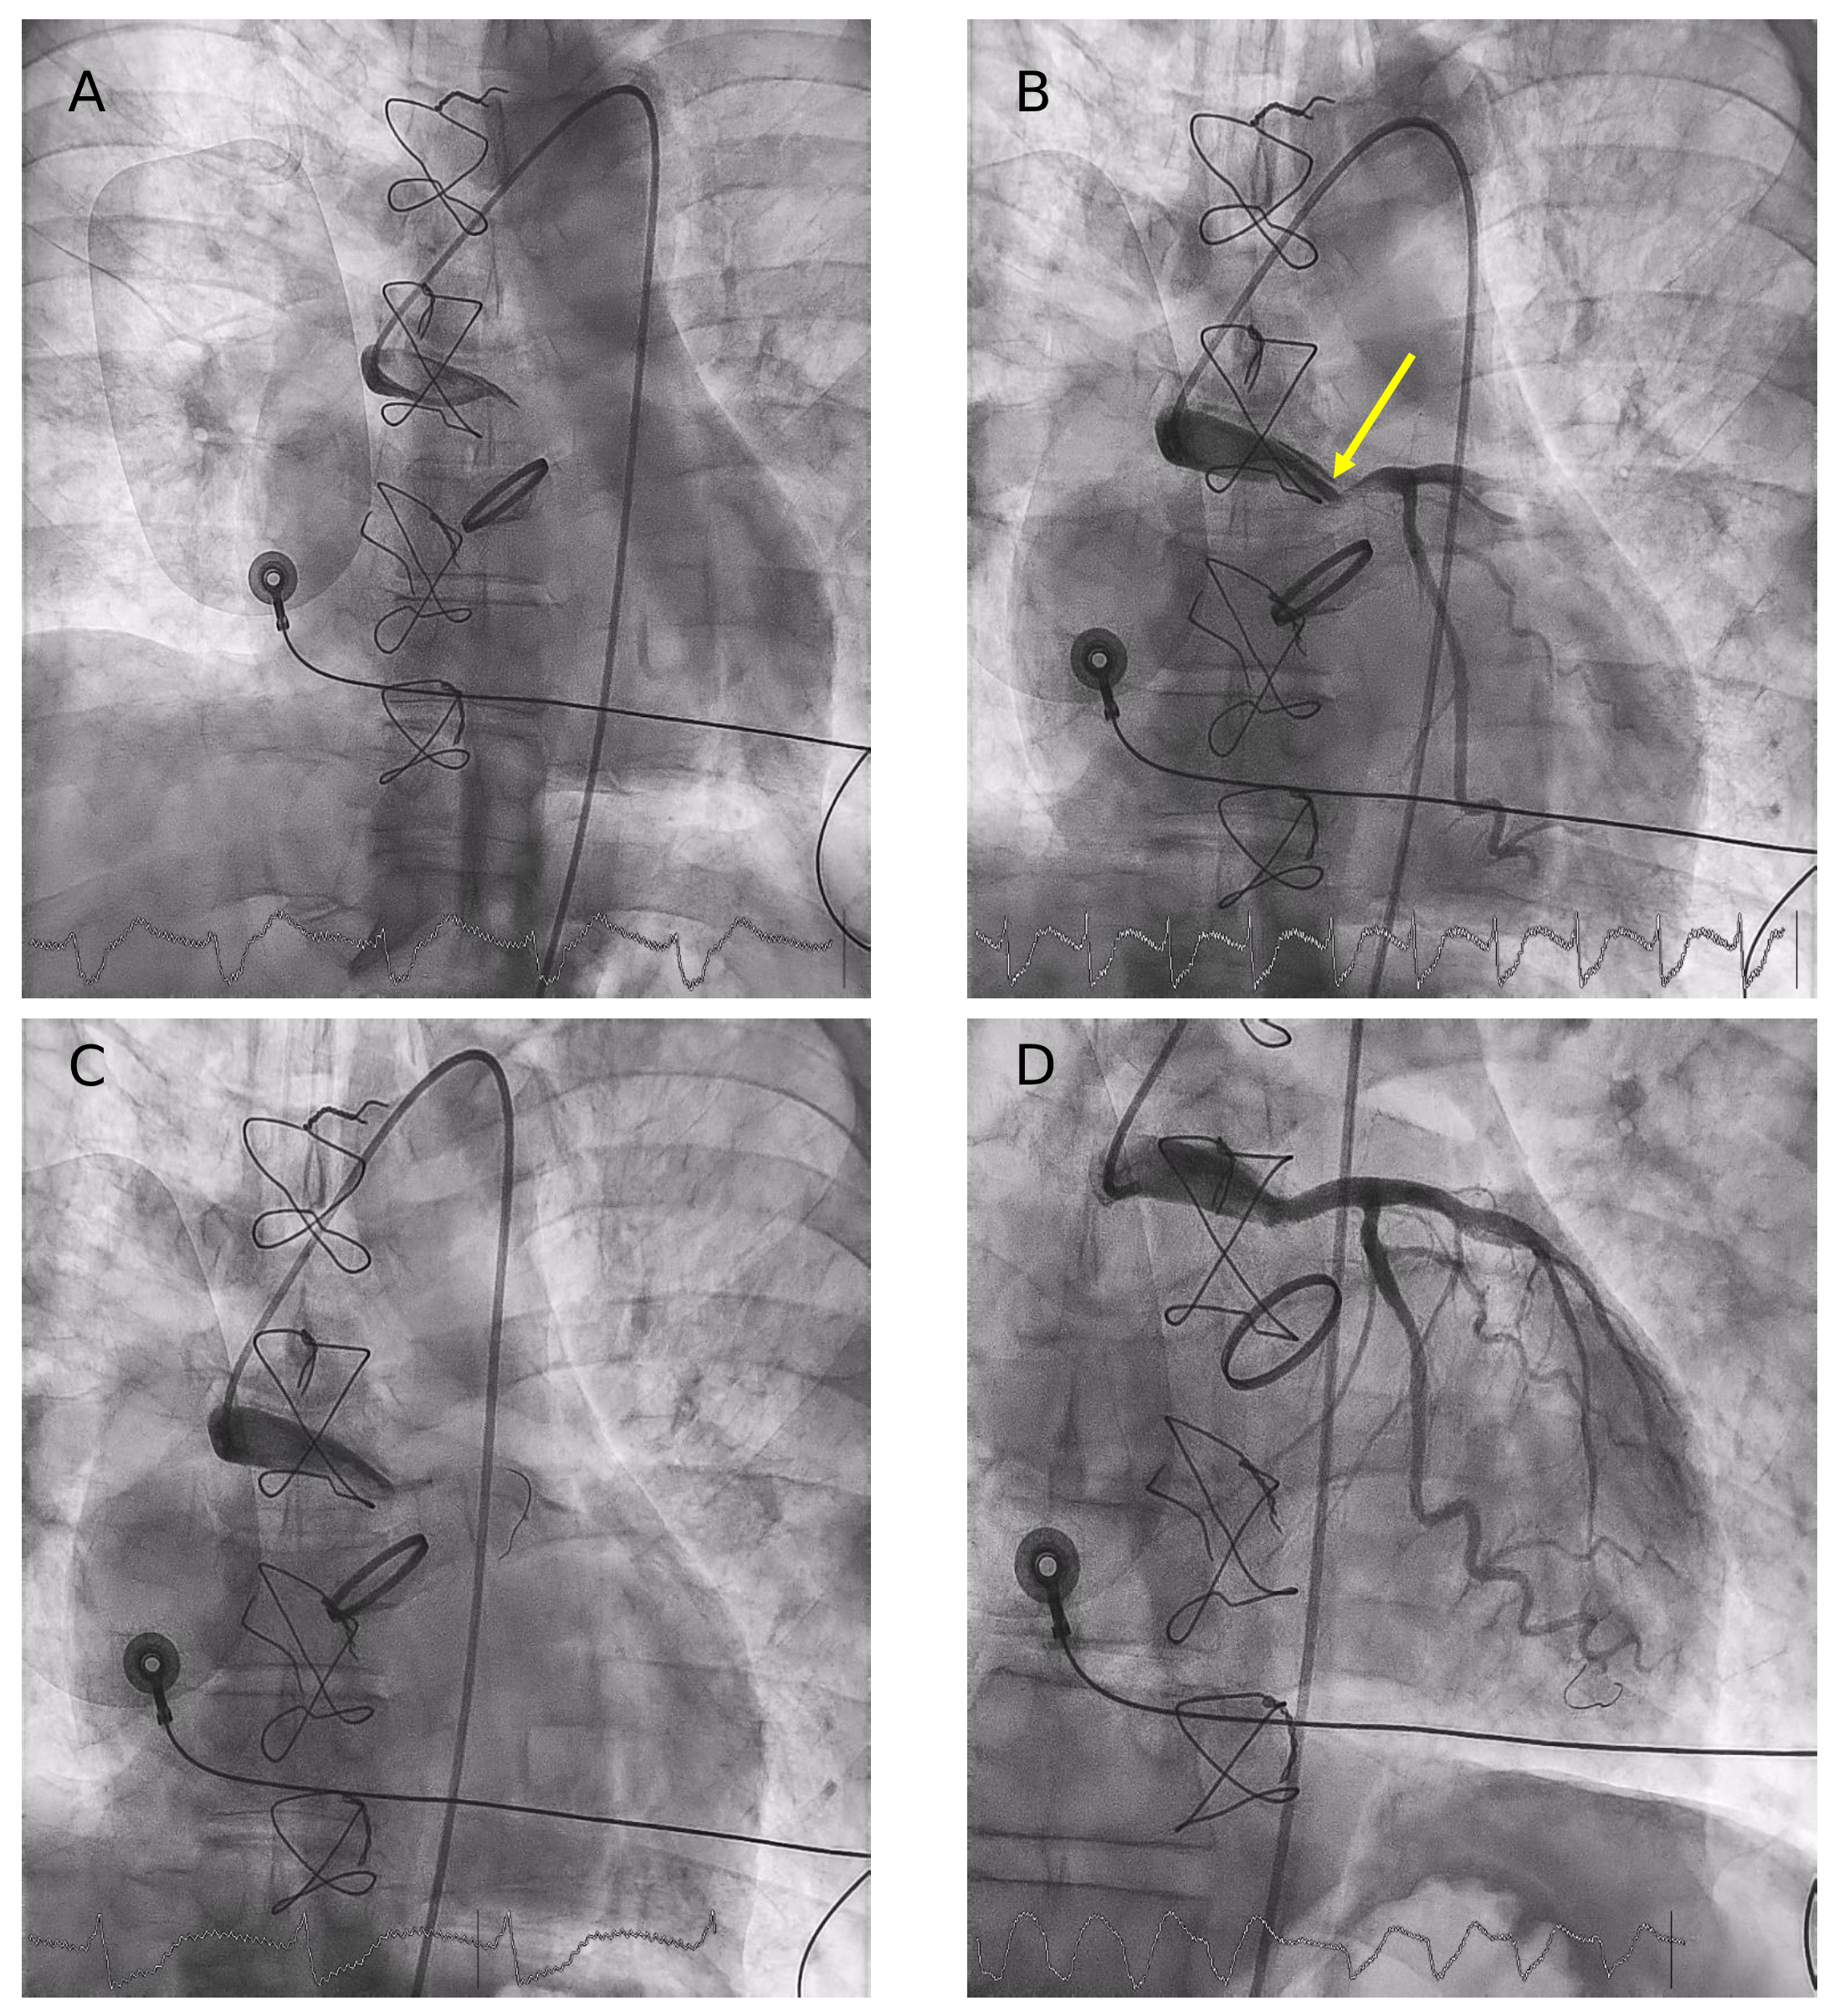

Because of pulseless ventricular arrhythmias, the patient required intubation and support with femoro-femoral veno-arterial extracorporeal membrane oxygenation (VA-ECMO) combined with an intra-aortic balloon pump. Cardiac computed tomography performed several days later confirmed the patency of both stents and the anatomical configuration of the graft (Figure 2).